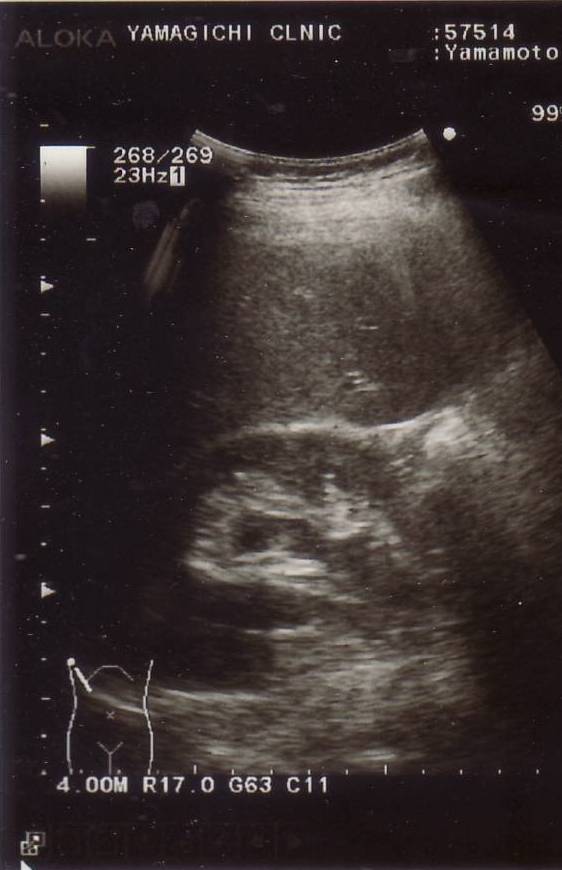

石が尿管に詰ま

り腎臓が尿で

浸潤した

2014年8月6日

(水)

腎臓が正常に

なった

2014年9月11日

(木)

僕の腎臓の超音波映像

偶然ですが、除菌5日目に右脇腹が猛烈に痛んだので、緊急に山口先生に見ていただき、腹部レントゲン撮影と超音波検査により、 何と、尿管結石にょうかんけっせきも発症したことが分かりました。 結石が尿管に詰まって、右図下左の超音波による腎臓じんぞうの画像のように、 腎臓が尿で浸潤しんじゅんしたのです。 この治療も投薬にてピロリ菌除菌と同時進行となりました。数日後に尿管結石は完治しました。その超音波画像が右図下右の腎臓画像で、正常になっています。 ピロリ菌の除菌の最中に、偶然、尿管結石を発祥するという不可思議なことでした。